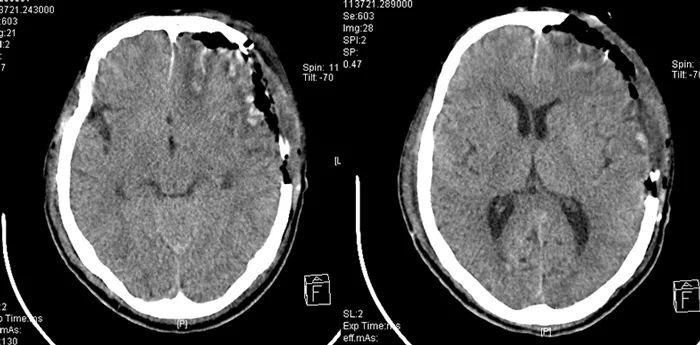

頭顱CT提示

左側(cè)額顳頂部硬膜下血腫

左側(cè)顳葉腦挫裂傷

枕骨右側(cè)骨折

右側(cè)眼球萎縮鈣化